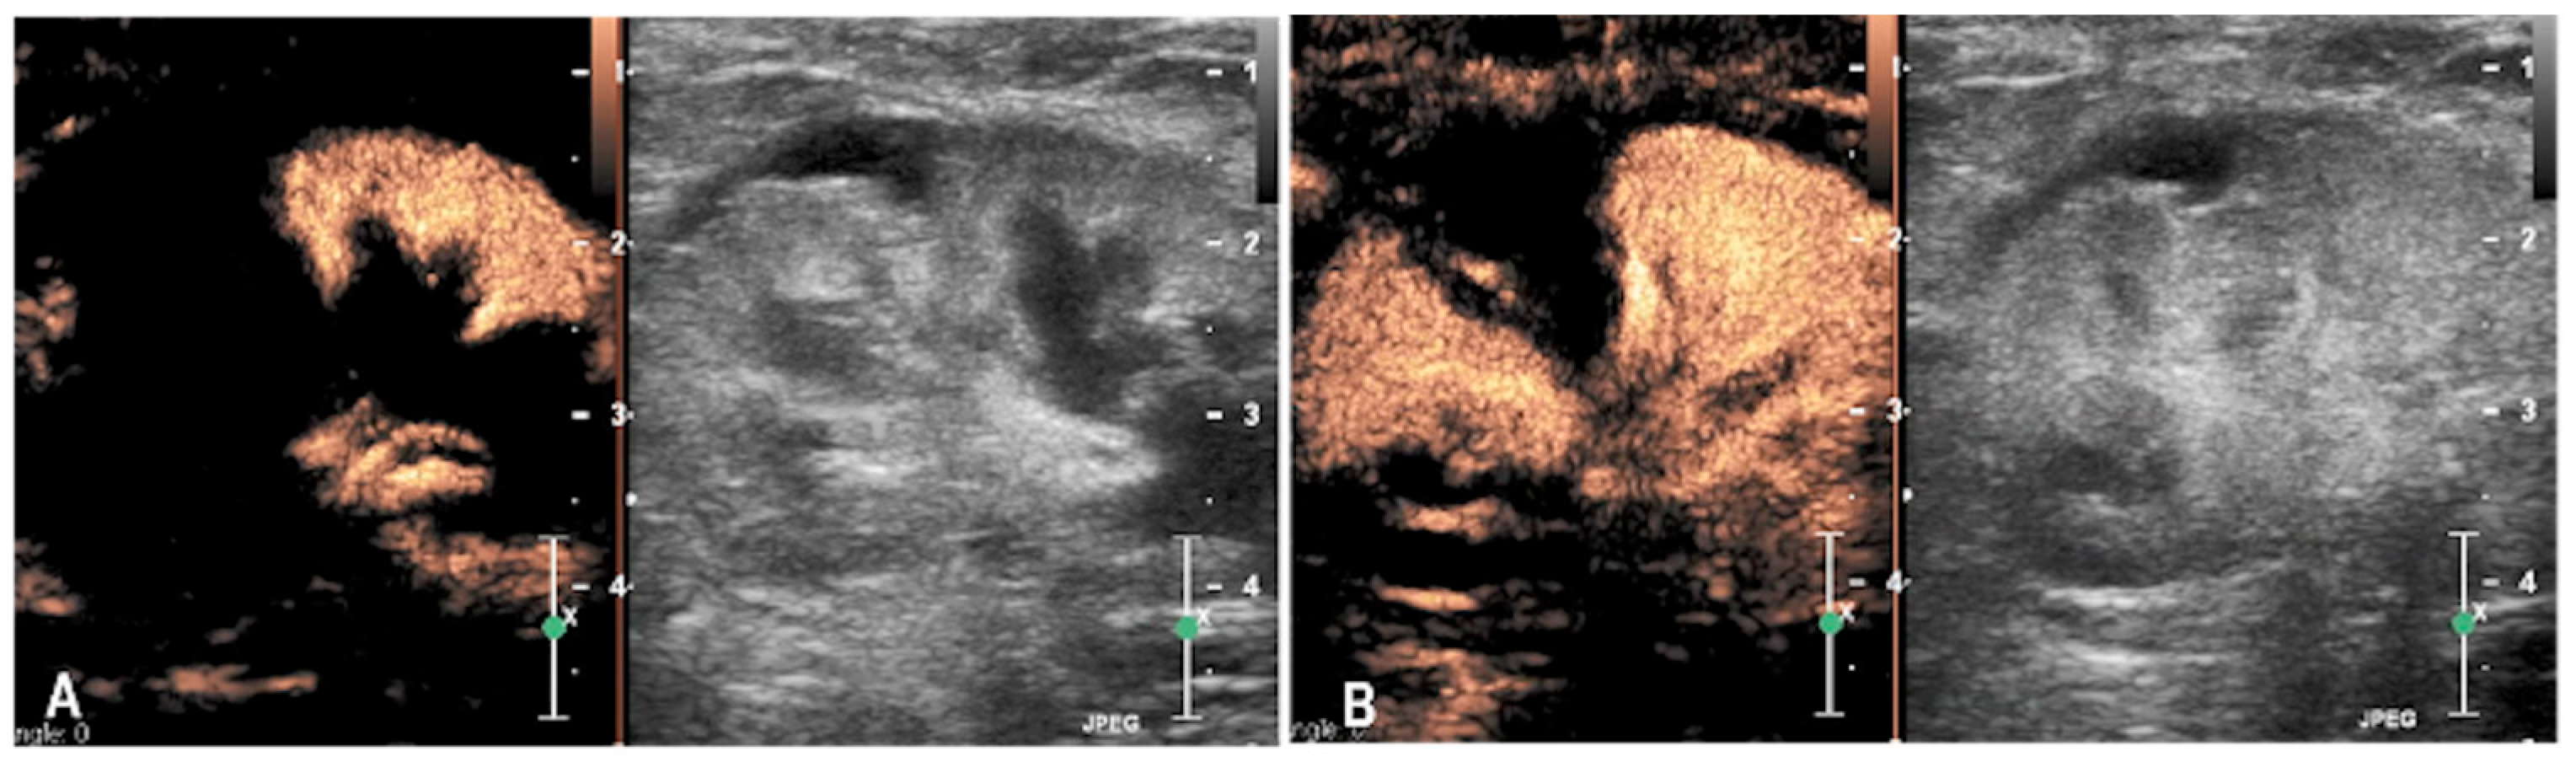

3.1. Case 1